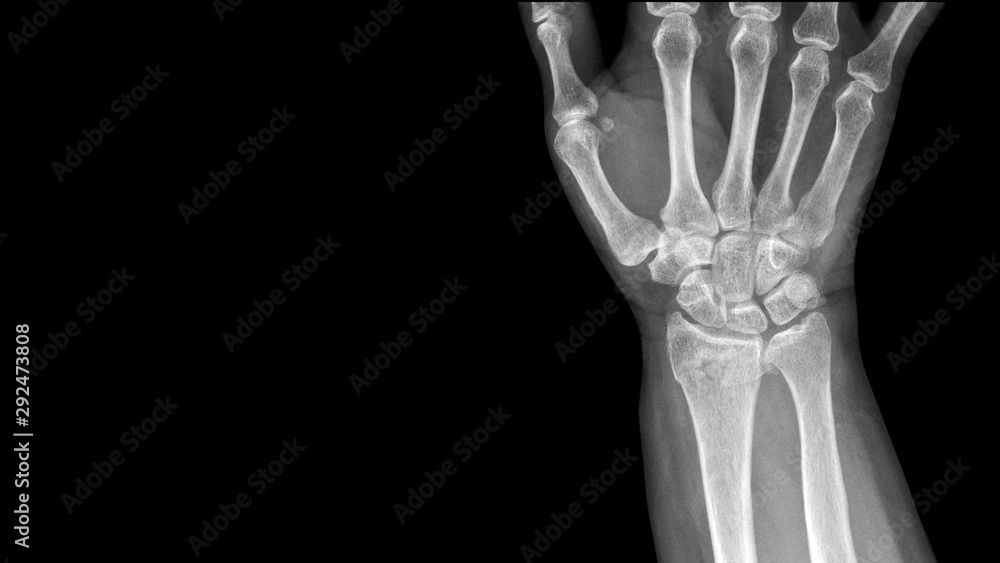

Film X ray wrist radiograph show wrist bone broken (torus or buckle fracture). The patient has Wrist Pain Nothing On X Ray Specialized views (e.g., posteroanterior in ulnar deviation, pronated oblique) and repeat radiography in. — wrist flexion (average maximum, 70 degrees), extension (70 degrees), ulnar deviation (40 degrees), and radial deviation (20 degrees) are. — wrist pain is often caused by sprains or fractures from sudden injuries. They can use a wrist x. Some conditions need additional imaging tests.. Wrist Pain Nothing On X Ray.